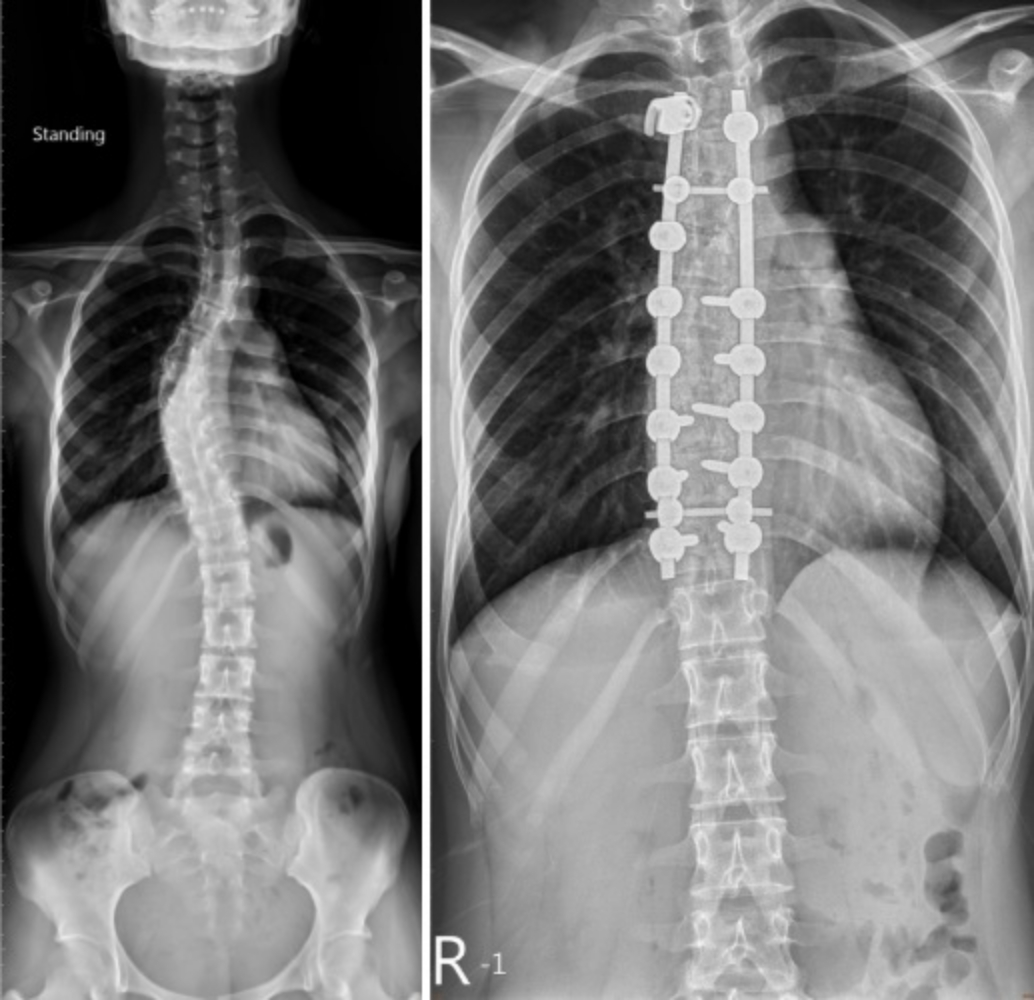

收治謝小姐的黃聰仁表示,經檢查發現,她的側彎角度已達40多度,經與病人及家屬解釋及討論後,決定以手術矯正。「謝小姐術後復原良好,背痛問題也消失,目前僅需每半年回院追蹤。」黃聰仁指出。

黃聰仁表示,治療上根據患者年齡及脊椎側彎的角度,「18歲以下青少年側彎角度20度以上者,建議每4-6個月追蹤,若角度沒有變化或者1年內角度增加未達5-10度,基本上不須特別治療,但要持續追蹤;側彎角度在25-40度者,則建議採用背架治療;若是角度達到40度以上者,才需要考慮是否採用手術矯正。」